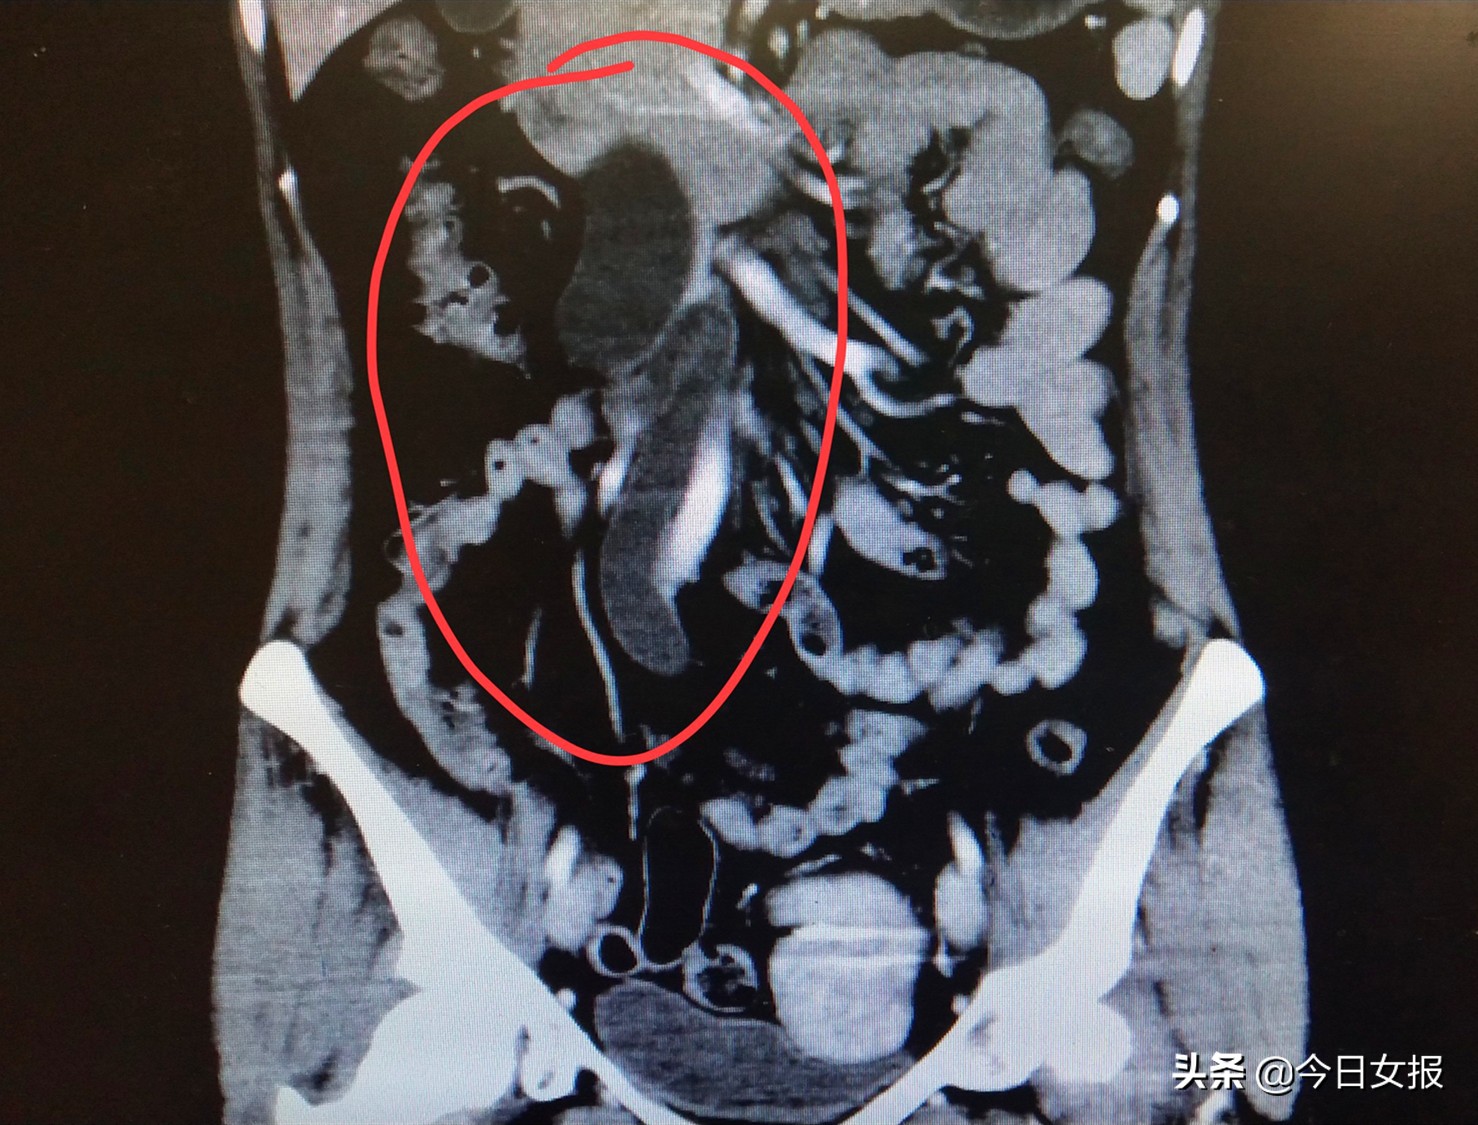

2020年2月,陈女士复查双肾B超显示:右侧输尿管狭窄、右肾重度积水。于2月初做了右输尿管镜检查+DJ管植入的手术,以扩张狭窄的输尿管并改善重度肾积水的情况。一个多月后,陈女士自觉腰痛无好转,提前到医院取掉DJ管,并于4月11日来到湖南省人民医院天心阁院区泌尿外科就诊。

李远伟主任医师检查发现,陈女士的阴道后壁有一个肿块,考虑右侧输尿管狭窄、右肾积水可能与此肿块有关,于是邀请妇科黄薇副主任医师会诊。做了妇科检查发现,患者阴道后方直肠前方右侧有一个硬硬的包块,初步考虑为深部子宫内膜异位症,这应该就是导致她输尿管扩张、肾积水的主要原因。

黄薇副主任医师组织科内大讨论,同时邀请泌尿外科李远伟主任医师、普外科刘祺主任医师,麻醉科等多科专家讨论后,于4月22日在全麻下为陈女士施行剖腹探查术。术中发现,右侧盆壁输尿管下段明显增厚,上段输尿管明显增粗,术中病理检查明确为子宫内膜异位症。黄薇副主任医师联合泌尿外科刘哲主任医师为患者施行右侧盆壁肿块切除、右输尿管粘连分离、右侧输尿管部分切除再植术。手术过程顺利,患者术后腰痛症状明显好转。

但陈女士属于深部浸润型子宫内膜异位症的一种特殊类型——输尿管内膜异位症,出现了输尿管狭窄及肾功能损害,所以腰痛持续出现,而不是与月经周期同步,从而增加了诊断的难度。